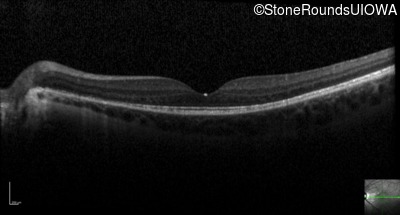

Optical Coherence Tomography - Right - 20/40 +1

Exemplar / OCT Stack